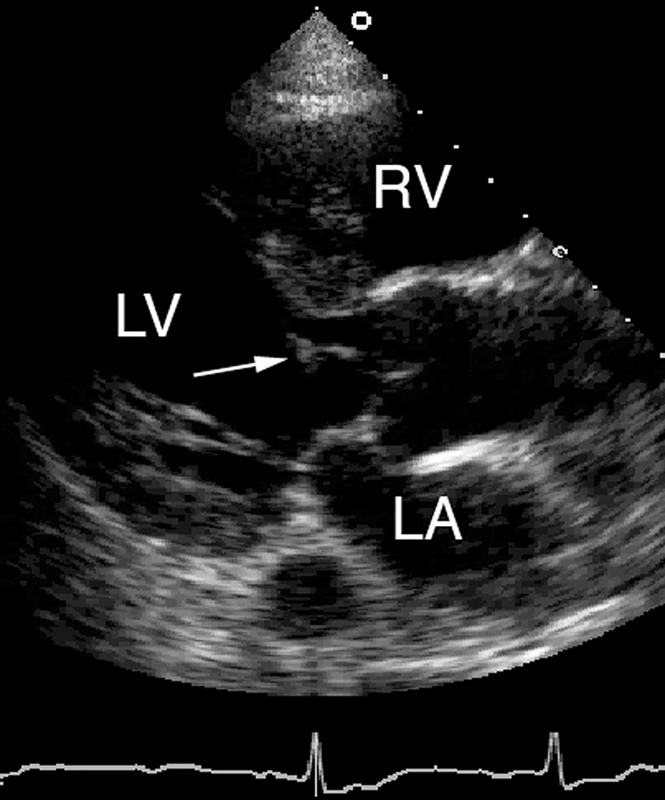

فحوصات تشخيصية لبعض امراض القلب والشرايين التاجية